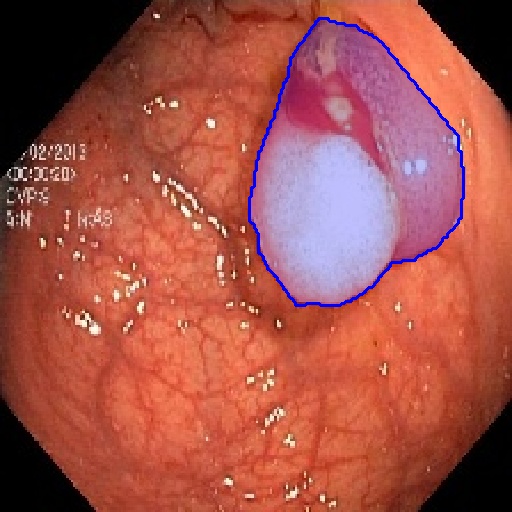

| Fine-Tuning | KvaSir [68] | 2D Endoscope | 1000 |

In 3D settings, we segment 2D slices and merge results for a 3D volume. We also benchmarked with 3D self-supervised methods from [86]. Tables (2) and (3) show that our two versions with ResNet-50 and Sam’s ViT hold the best records in each category. For instance, we outperform 2D SSL methods trained on the same dataset, surpassing foundation models such as SAM, Flava, and Clip. In the prompt-based settings, LVM-Med also delivers better performance compared with SAM. Second, LVM-Med achieves the best overall results on seven of eight segmentation tasks, mostly held by LVM-Med with ResNet-50. The improvement gaps vary on each dataset, for e.g., from on Kvasir and BUID compared with 2D supervised methods.